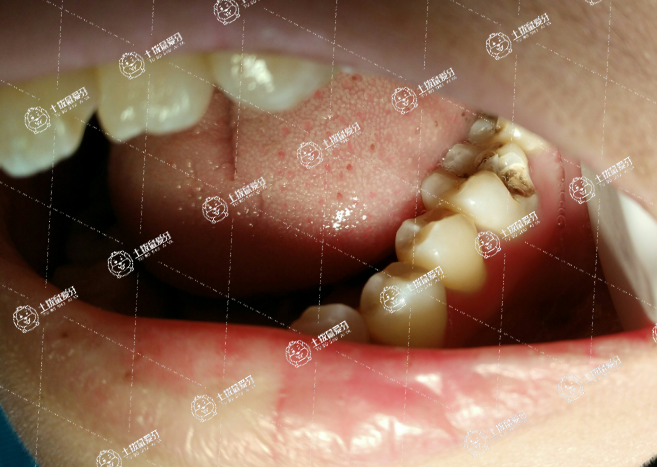

樹脂補牙是治療齲齒的方法,使用樹脂材料對齲洞進行充填。

樹脂是齲齒充填的材料,顏色可選擇,近似牙齒的顏色。目前臨床上使用的樹脂材料多是需要光固化燈進行固化成型的。樹脂固化前是軟的,可以塑形,固化后堅硬,美觀耐用。

補牙是對蛀牙進行清理,去除牙齒腐爛的部分,用充填材料恢復牙齒外形,發(fā)揮牙齒的咀嚼作用并恢復美觀。